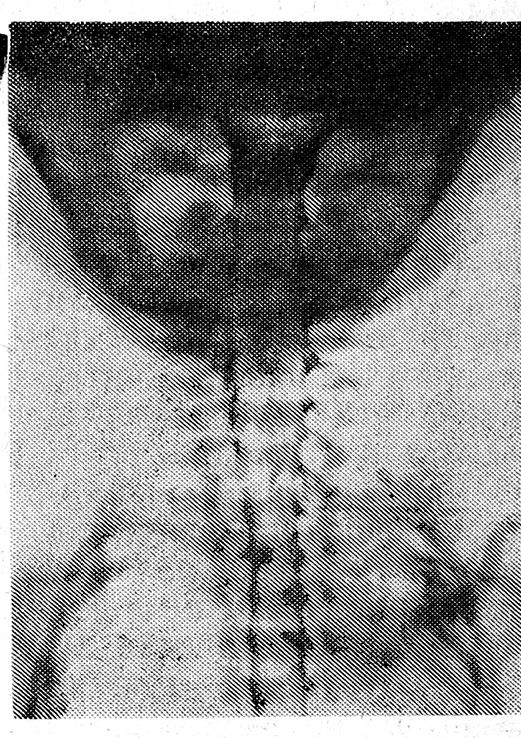

Рис. 1. Постмортальная мие- лограмма и ангиограмма в боковой, проекции новорожденного Р. На уровне С2 позвонка определяется блокада спинномозгового канала из-за переднего вывиха С2—Сз. Заднее смещение передней спинальной артерии на уровне C1—С4 обусловлено эпидуральной гематомой.

Рис. 2. Постмортальная миелограмма в прямой проекции новорожденного М. На уровне С2—С3 позвонков видно сдавление спинного мозга из-за выпадения хрящевого диска

Рис. 3. Постмортальная миелограмма в прямой проекции новорожденного Г. Веретенообразное утолщение поврежденного спинного мозга после самовправившегося вывиха атланта.

При рентгеноконтрастных исследованиях субарахноидального и эпидуральногопространства установлены повреждения спинного мозга, обусловленные сломанным или вывихнутым позвонком. Сужение позвоночного канала варьировало от незначиг тельнош до полного закрытия просвета. Смещение позвонка, как правило, происходило кзади, при этом на обычных рентгенограммах смещению позвонка соответствовало почти вдвое большее сужение просвета канала на патологоанатомических препаратах: вследствие перемещения тело позвонка приближалось к дуге и суставный отросткам вышележащего позвонка, одновременно суживая позвоночный канал. Возникшее сужение позвоночного канала более наглядно! и точно выявлялось в процессе рентгеноконтрастных исследований пространств спинного мозга (рис. 1).

У трупов 3-й группы при рентгенографии позвоночника костных повреждений не обнаружено; изолированный ушиб спинного мозга и ишемия рентгеноморфолопически распознаны на пневмомиелои миелограммах у 39 трупов. Самовправившиеся вывихи у 13 трупов не вызывали существенного сужения позвоночного канала, однако на пневмюмиелограммах наблюдалось не вполне равномерное веретенообразное утолщение спинного мозга, занимавшее весь шейный отдел или его часть и суживавшее субарахноидальное пространство вплоть ДО' перерыва констрастирования.' Отек спинного мозга вследствие его ишемии, обнаруженный у 26 трупов, тоже проявлялся равномерным утолщением спинного мозга, суживающим субарахноидальное пространство. Протяженность и выраженность утолщения зависели от тяжести нарушений кровообращения. Оно соответствовало уровню позвонков Сг и Сз или занимало весь шейный отдел, имело гладкую поверхность и носило веретенообразный характер с очень плавным переходом к неизмененному участку (рис. 3).